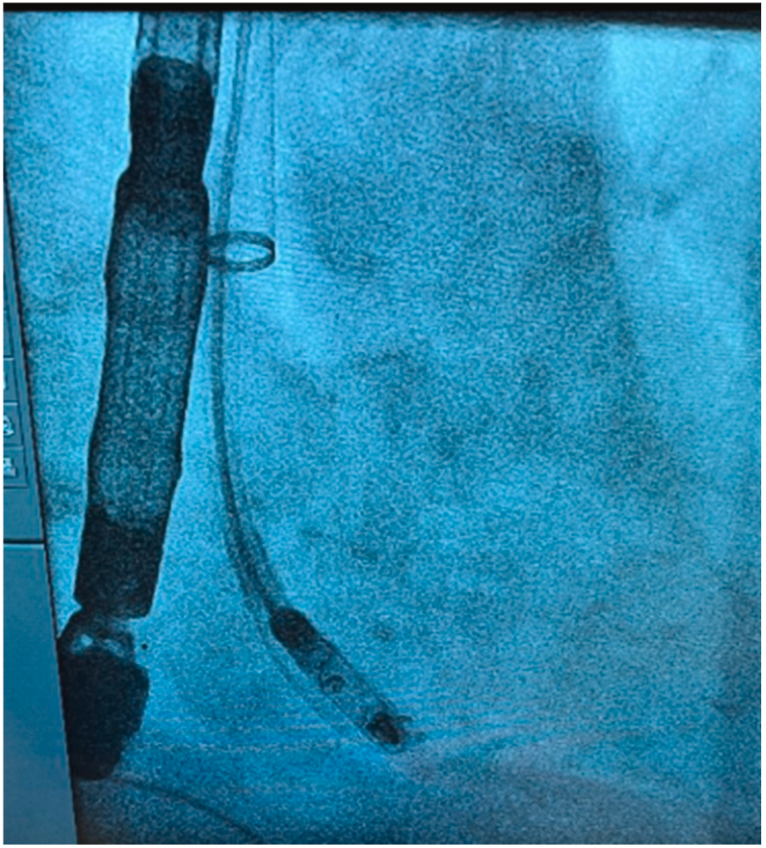

· 移除AVEIR™ VR起搏器输送导管后,通过同一根27Fr外鞘将装载AVEIR™ AR起搏器的新输送导管送入右心房;通过在上腔静脉与右心房交界处调弯,使导管形成J形弯曲,从而让AVEIR™ AR起搏器向上指向(图3A、B、C),定位右心耳目标位置并完成Mapping标测,但因旋入后损伤波形消失,需重新更换位置;

图3A RAO下导管在上腔静脉与右心房交界处的初始弯曲

图3B RAO下右心耳造影

图3C RAO下机器旋入前位置